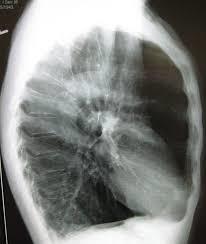

What is a common gross/x-ray appearance in emphysema

Barrel-shaped chest